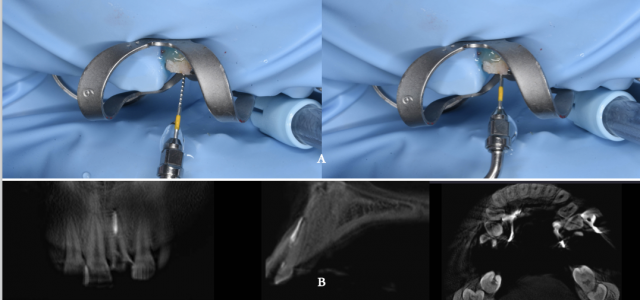

① 21 去除原根管口的暂封物,40号K锉探查根管,测量工作长度为19.5mm,拍试尖片确定达根尖区,手动K锉联合机动镍钛器械预备根管至#40/06,术中5.25%NaOCl+17%EDTA交替冲洗,终末生理盐水冲洗,吸干,导入VitaPEX糊剂,玻璃离子暂封两周。

术中治疗 A.EDTA润滑根管;B.手用扩锉针根管疏通;C.5.25%NaOCl与生理盐水交替冲洗;D.机用马达根管预备

检查 :21暂封存,无叩痛。

处理:21 去暂封物,3%NaOCl与17%EDTA结合,超声锉被动荡洗去尽VitaPEX糊剂,干燥根管,试主牙胶尖,AH-Plus+热牙胶垂直加压充填技术充填中下段根管,X线片确认根管下端充填质量良好。酒精棉球玻璃离子暂封一周。

术中治疗 A.超声根管荡洗;B.热牙胶充填后影像

术中治疗 A.桩道预备完成;B.纤维桩试合;C.充填树脂水门汀;D.纤维桩就位